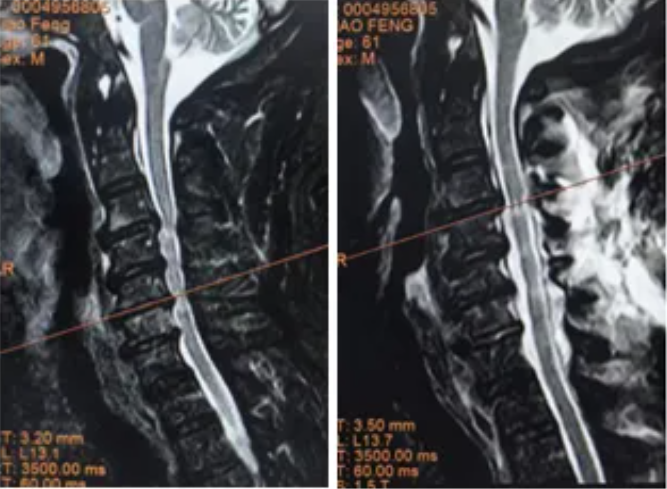

▲ 术前MRI ▲ 术后MRI

术后影像显示患者椎管空间明显扩大,脊髓压迫解除,四肢麻木症状消失,肌力逐渐恢复,生活质量显著提升。